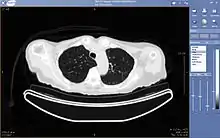

Teleradiology

Teleradiology is the ability to send radiographic images (x-rays, CT, MR, PET/CT, SPECT/CT, MG, US...) from one location to another.[69] For this process to be implemented, three essential components are required, an image sending station, a transmission network, and a receiving-image review station. The most typical implementation are two computers connected via the Internet. The computer at the receiving end will need to have a high-quality display screen that has been tested and cleared for clinical purposes. Sometimes the receiving computer will have a printer so that images can be printed for convenience.

The teleradiology process begins at the image sending station. The radiographic image and a modem or other connection are required for this first step. The image is scanned and then sent via the network connection to the receiving computer.

Today's high-speed broadband based Internet enables the use of new technologies for teleradiology: the image reviewer can now have access to distant servers in order to view an exam. Therefore, they do not need particular workstations to view the images; a standard personal computer (PC) and digital subscriber line (DSL) connection is enough to reach keosys central server. No particular software is necessary on the PC and the images can be reached from wherever in the world.

Teleradiology is the most popular use for telemedicine and accounts for at least 50% of all telemedicine usage.